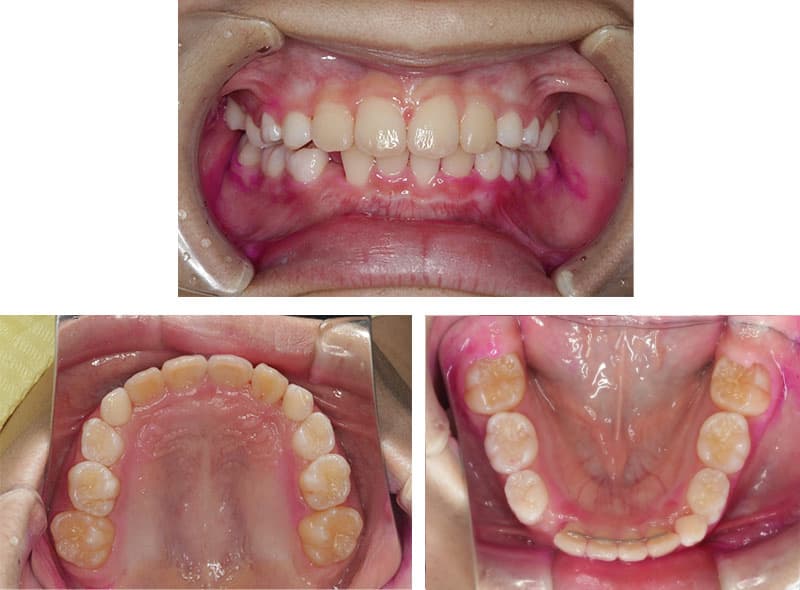

当院では、小児矯正を専門に行い、お子様の将来の歯並びや噛み合わせを考えた治療をご提供しています。歯並びの乱れは見た目だけでなく、噛み合わせや発音、むし歯リスクにも影響を与えるため、早めのケアが大切です。「いつから矯正を始めたらいいの?」「どんな治療方法があるの?」など、矯正に関する疑問やお悩みがありましたら、ぜひ一度当院にご相談ください。当院では、痛みが少なく負担の少ないマウスピース矯正を導入し、お子様の成長に合わせた矯正治療を行っています。まずは無料相談で、お子様の歯並びの状態をチェックし、最適な治療プランをご提案いたします。お子様の健やかな成長と美しい笑顔を守るために、当院がサポートいたします!

症例の詳細はこちら